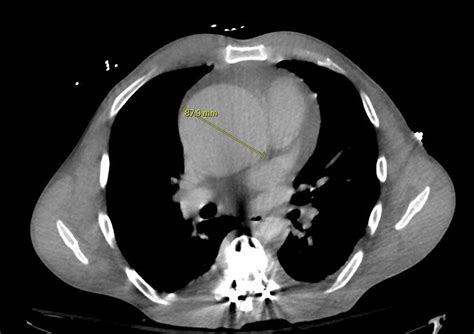

To diagnose the extent of the dilation, clinicians utilize non-invasive imaging techniques. An echocardiogram is the primary tool used to measure the diameter of the aortic root. If further detail is required, a cardiac CT scan or MRI provides a comprehensive three-dimensional view of the aorta, allowing surgeons to plan potential interventions.

CT Angiography High-resolution mapping As needed/Pre-surgical